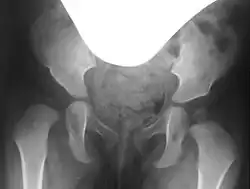

Hip dysplasia on the right (left in the image), with a steep acetabulum and absent acetabular rim, and a poorly formed femoral head

In hip dysplasia, the femoral head lacks sufficient lateral and anterior coverage, known as the acetabular rim. This inadequate coverage can cause the femoral head to slip upward and, depending on the severity, may lead to dislocation of the hip.[3]

Severe hip dysplasia on the right, with inadequate and overly steep lateral coverage